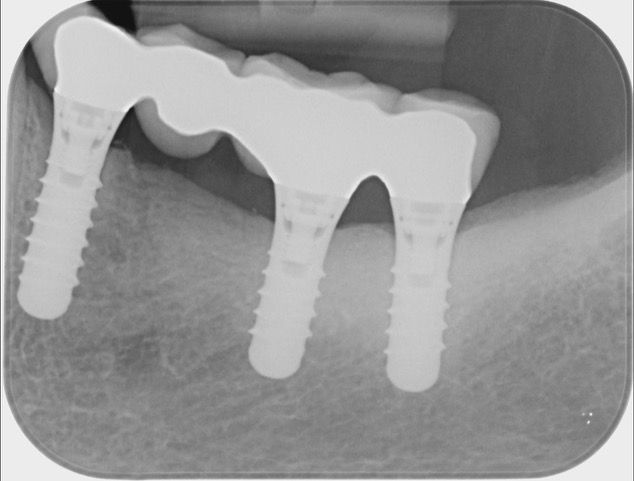

Riabilitazione di un segmento laterale edentulo con

posa di impianti e rigenerazione ossea

Segmento laterale edentulo

Posa impianti nel 2006

Situazione stabile dopo 19 anni